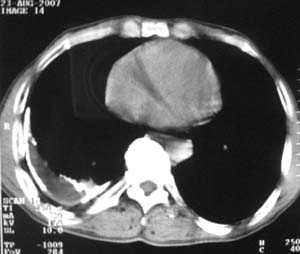

标题: CT9556:男,54岁,包裹性积液,请各位老师会诊其原因! [打印本页]

男,54岁,无任何不是感.体检发现右肺部阴影.现行ct进一步确诊.

右侧胸廓塌陷,肋间隙变窄,肋骨增生变粗,脏壁层胸膜肥厚、钙化。符合陈旧性结核性脓胸改变

右侧包裹性积液伴胸膜钙化.

包裹性积液伴胸膜钙化,考虑结核性